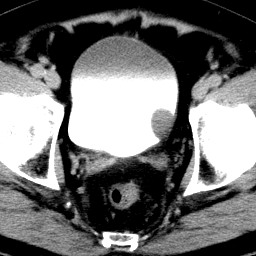

男,79岁,无痛性肉眼血尿1周。

由膀胱左侧后壁向内突出一圆形肿物,边缘光滑伴钙化,内密度均匀。支持考虑:膀胱癌!

蛋壳样钙化------应该是良性病变的影像表现。期待病理。

膀胱ca并肿瘤表面钙质沉积

膀胱左后侧壁可见软组织块影宊向腔内,边缘钙化,考虑膀胱占位,癌可能性大。

术后病理示:膀胱乳头状癌。